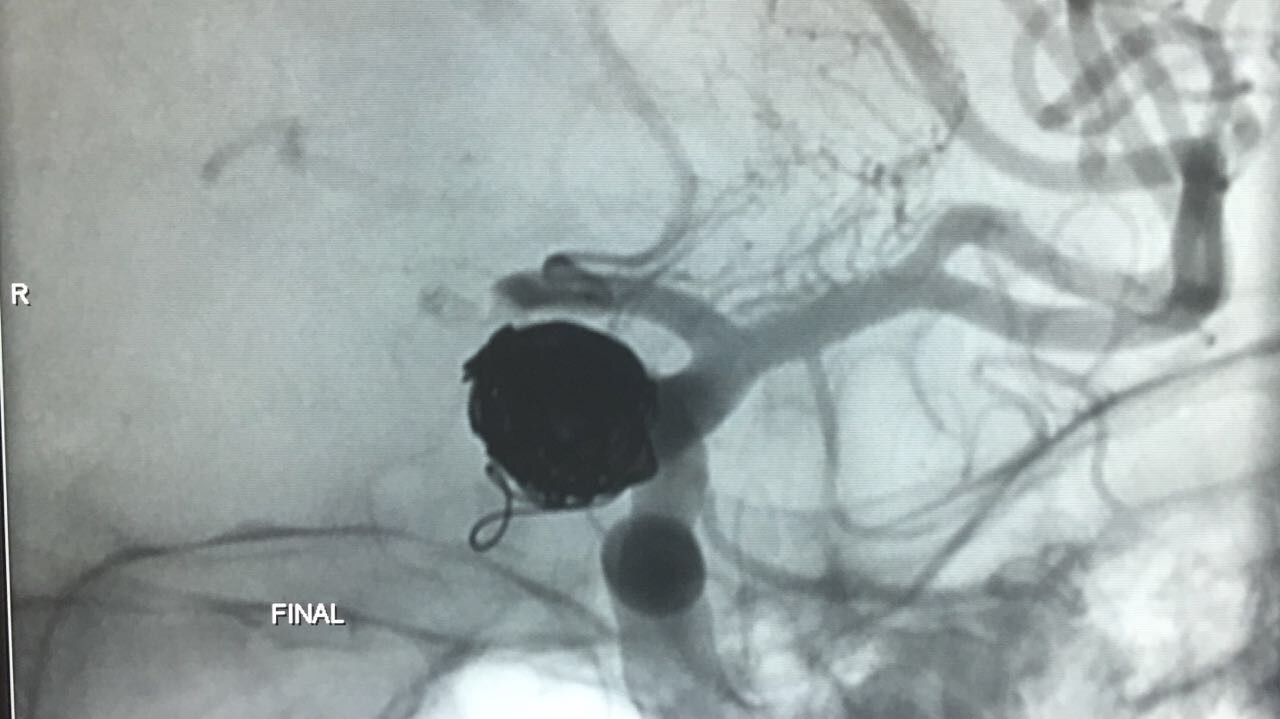

Embolização de Aneurisma segmento Oftálmico

Paciente foi então encaminhada ao setor de hemodinâmica sendo realizado Angiografia cerebral Digital e evidenciado aneurisma de segmento oftálmico da artéria carótida interna esquerda. Realizado embolização do aneurisma com microespirais, sem intercorrências. A paciente permanece em bom estado geral e neurológico recuperando em pós operatório imediato.